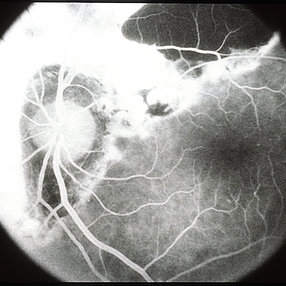

Thick Subretinal Hemorrhage 10

Mar 14 2013 by Maurice F. Rabb

59-year-old black woman with a thick subretinal hemorrhage with vision 20/20. The barrier laser was extended, but the hemorrhage not treated.

Condition/keywords: 20/20, subretinal hemorrhage